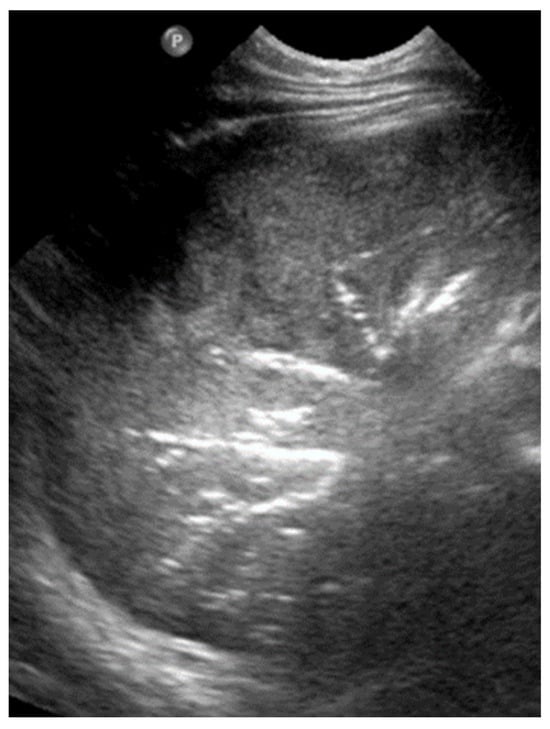

According to severity of the lung or interstitial pathology, B-lines may be solitary, few, multiple or even coalescent (Figure 2b), resulting in three imaging patterns associated with increasing severity: black lung, black and white lung, or white lung (Figure 3) [20,21].

Figure 3.

Black, black and white, white LUS patterns. (Stars: ribs).